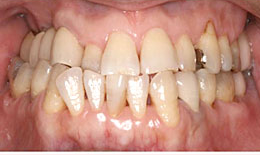

インプラント症例(5) 58歳 男性

治療前

治療後

治療方法

上顎

保存困難な歯を抜歯後、インプラントを2本埋め込んで、セラミックスクラウンを被せた

下顎

インプラントを2本埋め込んで、セラミックスクラウンを被せた